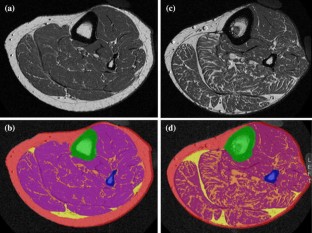

Fig. 1